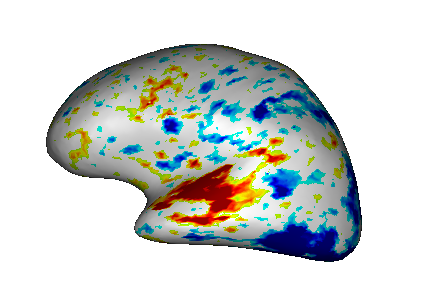

Fusion between an inflated cortical surface mesh and an activation map¶

Load:

White matter mesh:

data_for_anatomist/subject01/subject01_Lwhite.meshInflated white mesh:

data_for_anatomist/subject01/subject01_Lwhite_inflated.meshActivation map:

data_for_anatomist/subject01/Audio-Video_T_map.niiT1 MRI:

data_for_anatomist/subject01/subject01.nii

Do a fusion between white matter mesh and the activation map as described in the previous section. You now have a Fusion3D object.

Do a fusion between the Fusion3D object and the inflated white mesh. The mode will be FusionTexSurfMethod. You now have a TEXTURED SURF object.

Place the TEXTURED SURF object into a

.

Fusion between an inflated cortical surface mesh and an activation map.¶

The steps order is very important because if you directly do a fusion between the inflated mesh and the map, then the result will be wrong. In fact the white mesh and the inflated mesh are two meshes sharing the same structure (number of vertices and polygons), only the location of vertices differ, so they can be assigned the same textures. But 3D fusions for mesh-map and inflated mesh-map do not produce the same result since in a 3D fusion, the 3D location of points is actually taken into account. So you have to fusion first mesh and map to make an activation texture processing the correct points location, and then report this texture onto the inflated mesh in the second fusion (textured surface).